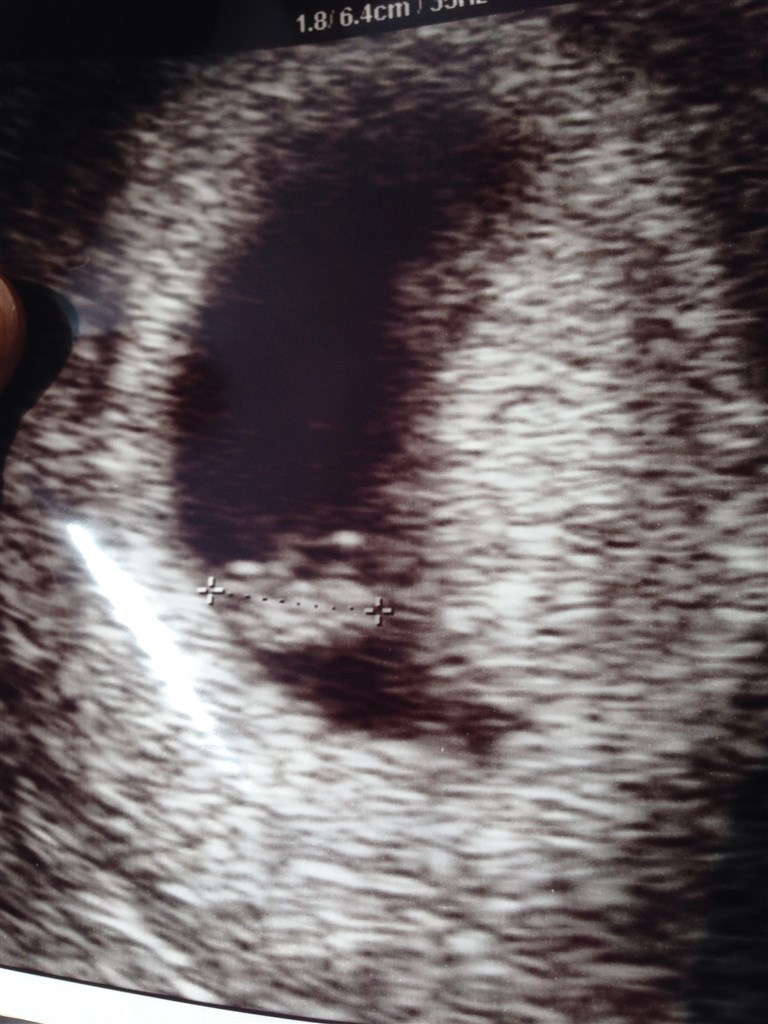

Jeg gav 500kr hos scanningsjordemoderen på Østerbro/Kbh. Bestilte igår og fik en tid i dag

fik nogle billeder og en dvd